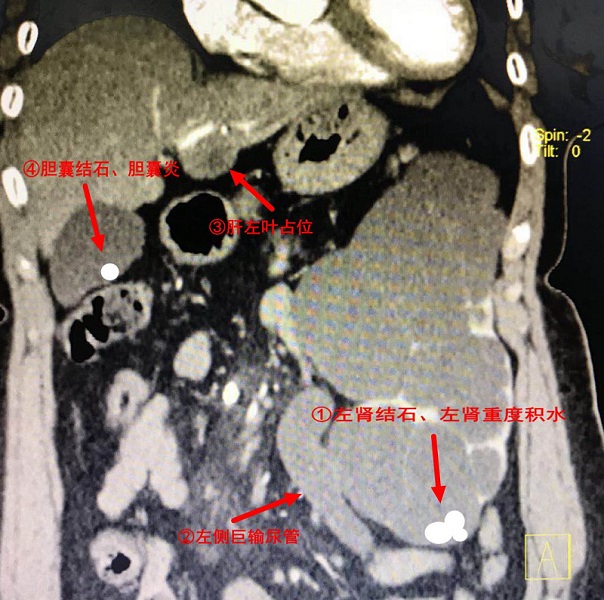

入院后,泌尿外科醫(yī)生們?yōu)槠牌磐晟屏烁黜?xiàng)檢查,其中CT檢查顯示左腎重度積水,皮質(zhì)菲薄,左腎多發(fā)結(jié)石,左側(cè)輸尿管全程擴(kuò)張;另外,還發(fā)現(xiàn)肝左葉占位性病變、膽囊結(jié)石、膽囊炎。

圖中紅色箭頭所指的分別是四個(gè)臟器病變

經(jīng)過(guò)同位素檢查,患者左腎已經(jīng)基本沒(méi)有功能,還合并了感染,需要手術(shù)切除;左側(cè)輸尿管全程擴(kuò)張,考慮先天性巨輸尿管癥,也需要手術(shù)切除。因CT提示肝臟有腫瘤,在肝膽胰脾外科的建議下患者做了MR檢查(核磁共振),不能排除肝臟是否惡性腫瘤!